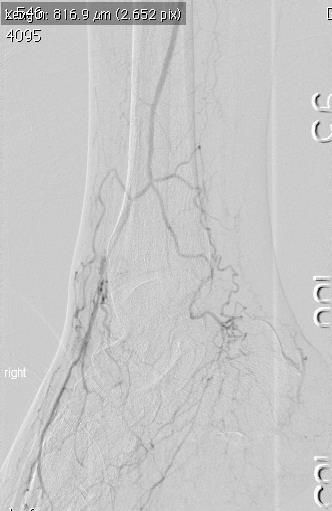

Careful selection of patients for artificial disc replacement is critical. There are several conditions that may prevent patients from receiving a disc replacement. These include spondylolisthesis (the slipping of one vertebral body across a lower one), osteoporosis, vertebral body fracture, allergy to the materials in the device, spinal tumor, spinal infection, morbid obesity, significant changes of the facet joints (joints in the back portion of the spine), pregnancy, chronic steroid use or autoimmune problems. Also, total disc replacements are designed to be implanted from an anterior approach (through the abdomen for lumbar). Patients may be excluded from receiving an artificial disc if they previously had abdominal surgery or if the condition of the blood vessels in front of the spine increases the risk of significant injury during this type of spinal surgery.

In addition to the potential complications associated with general anesthesia, the complications associated with artificial disc replacement may include breakage of the metal plate, dislocation of the implant, infection, nerve injury and injury to blood vessels and urological structures. To help minimize complications associated with the implant itself, proper selection of patients and size of implant is very important. Also, artificial implants may fail over time due to wear of the materials and loosening of the implants.